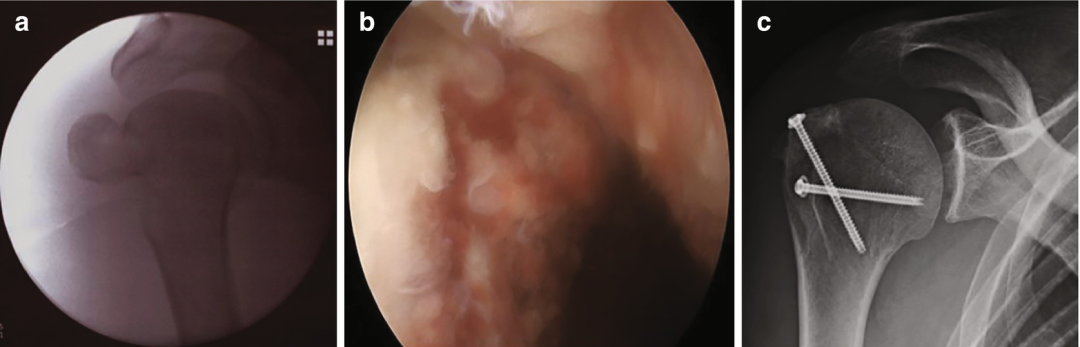

器械选择与肩袖修复术一致。采用缝线抓钳及套索穿刺器完成肌腱/骨块穿刺与复位。对于伴小骨壳的骨性撕脱骨折,应用缝线桥接技术(经骨等效修复技术)固定骨块:内侧排使用带线锚钉,外侧排采用免打结锚钉;亦可选择加速桥接技术(speed-bridge)。若大结节骨块完整致密,则优先选用螺钉固定——在关节镜监控复位后,经皮植入3.5~4.0mm中空螺钉,建议加用垫片以增强骨折线侧方加压并防止螺钉头陷入大结节外侧骨皮质。通常两枚螺钉即可实现稳定固定(图7)。

图7 大结节移位骨折合并肩袖后上部骨性撕脱术中影像(a) 移位的大结节骨折;(b) 关节镜见肩袖后上部骨性撕脱;(c) 术后X线示解剖复位及两枚中空螺钉位置

手术始于标准后方入路的诊断性探查。需系统检查并记录关节内结构(二头肌锚点、滑车系统、盂唇、盂肱软骨、韧带及肩袖),探钩评估组织完整性。通常因肩袖骨性撕脱导致足印区骨缺损显露松质骨。随后将关节镜转入肩峰下间隙并建立外侧入路,使用刨刀或电凝设备彻底清除肩峰下-三角肌下滑囊。将镜头切换至外侧入路直视骨缺损,以刨刀清理血凝块使骨块精确复位。

内侧排锚钉植入前,需用抓钳评估撕裂形态:牵拉骨块可明确肩袖回缩方向。因骨性解剖改变,常需接受非完美复位的妥协。根据缺损宽度选择1-2枚内侧排锚钉(推荐双线5.5mm PEEK螺旋锚钉,Arthrex),置入肱骨头软骨缘内侧骨折线处。经后方入路引入90度直型套索穿刺器,于腱-骨界面(滑囊侧至关节侧)穿透肩袖组织,探及肌腱与骨块移行区。缝线间距需保持8-9mm,打结后将缝线交叉固定至大结节外侧壁(骨折线远端)。术中需彻底清除该区域软组织(骨膜/滑囊)以实现清晰暴露。

外侧排采用1-2枚免打结4.75/5.5mm PEEK旋锁锚钉(Arthrex)。旋紧前需C型臂确认解剖复位,过度牵拉缝线可能导致骨块过度复位(通常无严重后果)。最后于旋锁锚钉表面剪断缝线(图8)。

图8 大结节移位骨折的影像学与术中技术图示

常规腋位X线片(图a)及CT扫描(图b)显示肱骨大结节(GT)移位性骨折。术中可见冈上肌肌腱(SSP)及冈下肌肌腱骨性撕脱(图c)。采用双排经骨等效缝合桥技术固定骨折块:内侧排使用2枚缝合锚钉,外侧排应用2枚无结锚钉(图d)。术后X线显示腋位(图e)及前后位(图f)骨折解剖复位。